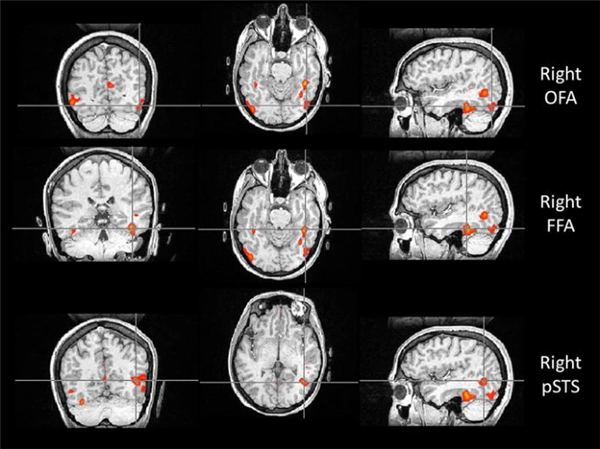

比如,位于枕叶的枕叶面孔区(Occipital Face Area, OFA),就像识脸网络的“先锋部队”。它专门处理眼睛、鼻子和嘴巴等五官“零部件”。当一张脸出现在我们眼前时,OFA 只需 约 100 毫秒 就能被激活,迅速对局部特征进行拆解,并将信息传递给 FFA 和上颞沟(Superior Temporal Sulcus, STS)。所以如果 OFA 出现问题,识别人脸就会变的很困难。

如果说 OFA 的作用是拆解五官,那么 STS 则更像是一个“动态解码器”。它对静态的面孔特征兴趣不大,却对动态特征极为敏感,尤其擅长捕捉 一颦一笑、眼神转动、嘴唇开合等细微变化。

正因为有 STS 的参与,我们不仅能认出“这是谁”,还能理解“他在表达什么情绪”“注意力投向哪里”,甚至在一定程度上推测对方的意图。STS 的参与也解释了为什么比起静态照片,在现实生活或视频中,我们更容易认出熟人。

与认脸有关的三个核心脑区,自上而下依次为:OFA(枕叶面孔区)、FFA(梭状回面孔区),以及 STS(上颞沟)。图片来源:doi: 10.1007/s00221-011-2579-1